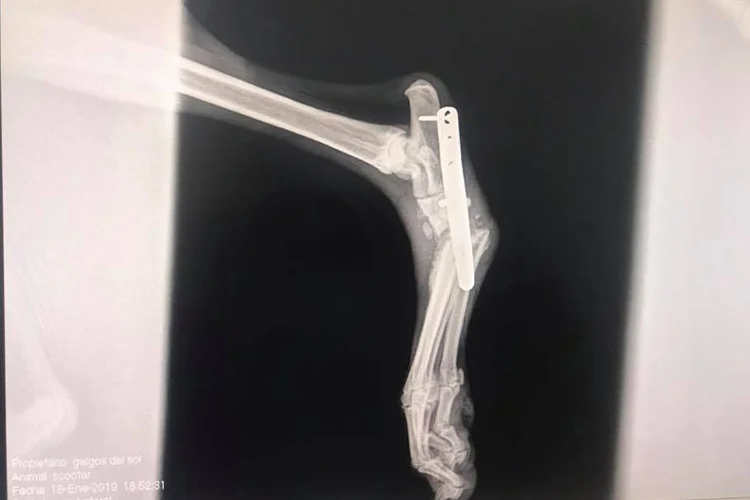

Scooter was rescued from the streets with a broken hock. Surgery has been completed and he is on the way to recovery. A very sweet cuddly boy, Scooter is clean in the house, loves other dogs and is very sociable. The hock is fully healed but he does limp when active.